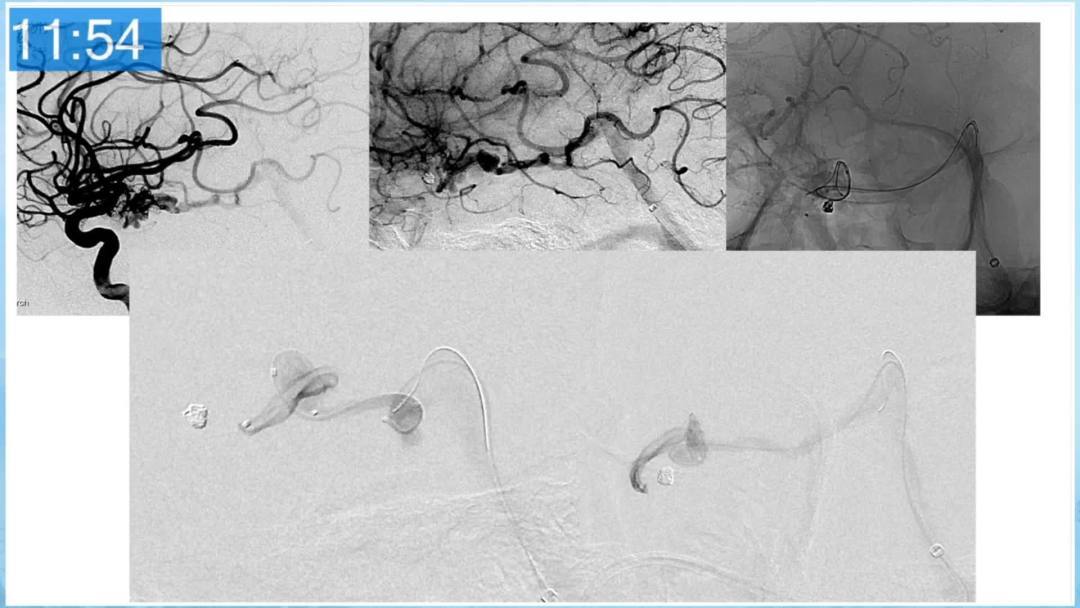

合理的复合平台下的综合治疗,针对每一个病变对应不同方法安全性分析,不预设、不排斥,每种技术发挥到最佳,互相保障。

本期为大家特别分享:空军军医大学唐都医院邓剑平教授的精彩会议内容《颅内动静脉畸形的复合手术治疗》,欢迎大家阅读和分享!